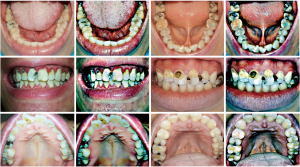

Due to the different progression of caries, there may not be enough contrast between the lesion and the surrounding normal areas, making the caries less distinctive. Using the multi scale retinex with color restoration (MSRCR) algorithm, the image parameters could be adjusted so that details such as color and texture of the caries were highlighted after enhancement. The caries could only be located in the enhanced area when the annotation position was the same as the enhanced area, so we reasoned that training the model only on the enhanced image may improve the accuracy of the model (Figure 6). Therefore, in this study, the dataset was image enhanced as the enhanced training set.

The results showed good caries recognition by the algorithmic model after learning on the combined training set Figure 7, comparing the test results of the 3 models, training the enhanced images together with the unenhanced images enhanced the model’s ability to recognize caries (Figure 8).

The mAP value of the original group training model for caries image recognition in the test set was 56.20%, in which the precision of primary caries was 76.92%, recall was 49.59%, F1-score was 0.60, and AP value was 55.63%; the secondary caries algorithm recognized 91.67% of precision, 52.38% of recall, F1-score was 0.67, and AP value was 56.78%. The mAP value of the enhance group training model for caries image recognition in the test set was 66.69%, and the primary caries algorithm recognized a precision of 81.82%, recall was 52.07%, F1-score was 0.64, and AP value was 68.21%; the secondary caries algorithm recognized 100% of precision, 33.33% of recall, F1-score was 0.50, and AP value was 65.17%. The mAP value of the comprehensive group training model for caries image recognition in the test set was 85.48%, with 93.33% for primary caries, 69.42% for recall, 0.80 for F1-score, and 85.09% for AP. The secondary caries algorithm had a precision of 100%, a recall of 52.38%, an F1-score of 0.69, and an AP of 85.87% (Table 1).